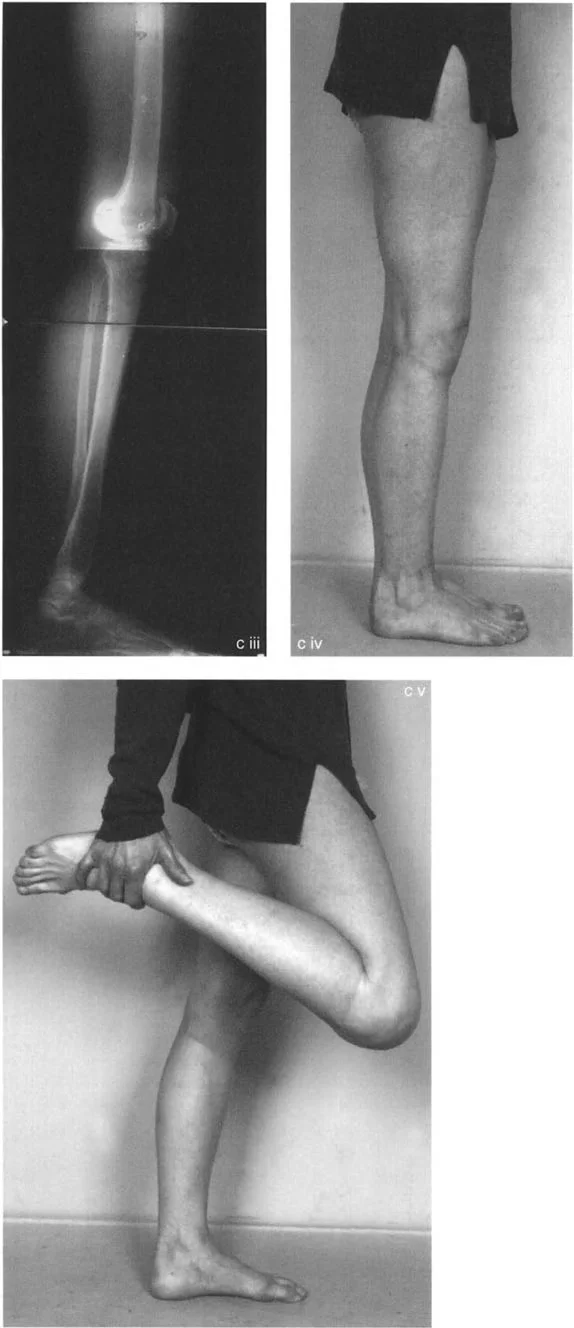

التقوس الخلفي الناتج عن كسور هضبة الظنبوب

يُعد التقوس الخلفي بعد الصدمة نتيجة متكررة لكسور هضبة الظنبوب الشديدة وعالية الطاقة (مثل كسور شاتزكر V أو VI). في هذه الإصابات، يتم "سحق" الهضبة المفصلية على الجزء الميتافيزي، وتلتئم في حالة منخفضة، بينما تظل الحدبة الظنبوبية متصلة بالجزء الأمامي البعيد.

في هذه الحالات الصعبة، قد يظهر المريض بمعايير إشعاعية شديدة. ليس من غير المألوف رؤية فرط استقامة سريري بمقدار 9 درجات أو أكثر، وزاوية PPTA غير طبيعية بشكل كبير تبلغ 108 درجات، وزاوية PDFA طبيعية نسبياً تبلغ 85 درجة.

غالباً ما يكشف الفحص السريري والإشعاعي عن تشوه لافت: تبرز الحدبة الظنبوبية بشكل واضح في مفصل الركبة الأمامي، وتعمل كعائق عظمي مادي للتمدد الكامل. علاوة على ذلك، يقع الجزء الخلفي من لقمتي الظنبوب بعيداً خلف لقمتي الفخذ، مما يؤكد الخلع الجزئي الخلفي المزمن.

تقنية قطع العظم على شكل حرف L

لتصحيح هذا التشوه المعقد، متعدد المستويات داخل المفصل والميتافيزي، فإن قطع العظم المستعرض القياسي غير كافٍ. تُعد تقنية قطع العظم على شكل حرف L هي الإجراء المفضل.

- التصميم: يتم تصميم قطع العظم بدقة لفصل الكتلة المفصلية المنخفضة عن الحدبة الأمامية. يمتد الجزء العمودي من "L" خلف الحدبة، بينما يمتد الجزء الأفقي أسفل الهضبة المنخفضة.

- التنفيذ: يسمح هذا للجراح برفع الكتلة المفصلية المنخفضة للأعلى وإمالتها للأمام، مع إعادة وضع الحدبة الظنبوبية إلى موقعها التشريحي بالنسبة لخط المفصل في نفس الوقت.

- التثبيت: يتيح استخدام جهاز إليزاروف أو إطار دائري سداسي الأرجل تصحيحاً تدريجياً ومتحكماً للتقوس الخلفي. توفر الأسلاك الدقيقة تثبيتاً ممتازاً في الجزء المفصلي القريب الصغير.

- النتيجة: استعادة كاملة لزاوية PPTA، وتقليل تشريحي للمفصل الظنبوبي الفخذي، وتطبيع مستوى إدخال وتر الرضفة.

تُظهر الصورة تخطيطاً لقطع العظم على شكل حرف L، وهي تقنية معقدة تستخدم لتصحيح التقوس الخلفي بعد كسور هضبة الظنبوب.

تُظهر هذه الصورة نتائج جراحة قطع العظم على شكل حرف L، مع استعادة المحاذاة التشريحية للركبة.